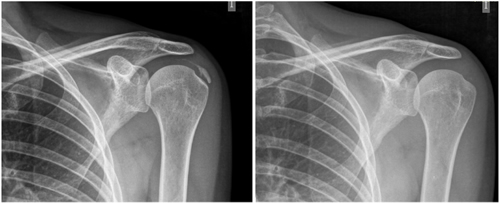

The average number of sessions in our series was 20. The criteria for continuing or stopping treatment was the radiological and clinical evolution (Figures 4 and 5). The interventions were performed up to a maximum of 40 sessions. Perrón treated patients for 9 sessions (3 weekly sessions for 3 weeks) (14). Leduc treated with 10 sessions (3 per week for the first two weeks; then one weekly for 4 weeks) (15). Rioja-Toro treated patients for 40 sessions (5 times per week) and evaluated them at 20 and 40 sessions (3). Chico-Álvarez treated patients between 15 and 30 sessions depending on the radiological evolution (5 times per week) (1).

Fig. 5. A 44-year-old female patient, with calcific tendinitis of the left supraspinatus, of the resorptive type, who after 20 sessions of iontophoresis decreased pain measured by VAS from 10/10 to 4/10, and calcification from 22 mm to 0 mm (complete disappearance).